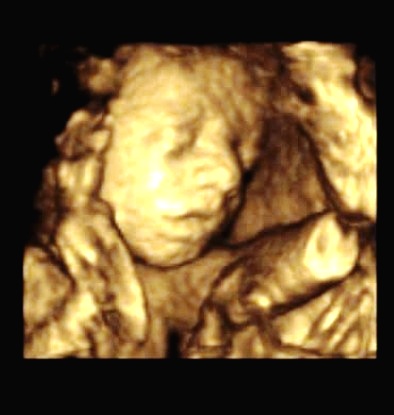

5.10.2010 - 1.UZ v poradně - 7.tt - Srdíčko krásně bije.

19.10.2010 - 2.UZ v poradně - 9.tt Fazolka má 11,1mm. Máme první foto.